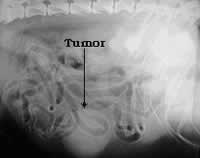

f) Algunos tipos de tumores